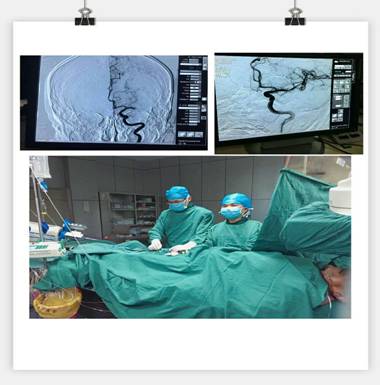

通訊員劉巧報道:10月21日,我院神經(jīng)內科成功實施靜脈溶栓聯(lián)合血管內介入治療的橋接搶救,成功救治了一位意識障礙的大面積腦梗塞的患者。

凌晨3點30分, “叮叮?!币魂嚰贝俚碾娫掜戔彺蚱屏松钜沟膶庫o。 “你好,這里是急診科,請準備一張男床,腦血管意外患者”?;颊呤且幻?3歲男性,突發(fā)右側肢體乏力5.5小時,由家屬用輪椅推送入院。入科后患者神志昏睡,心率48次/分,血壓186/100mmHg,NIHSS評分20分。病人情況十分危急,在劉禮泉主任指示下,患者為急性缺血性卒中,有溶栓指征。在劉主任與家屬談話期間,值班醫(yī)生同時開出醫(yī)囑,患者予以硝普鈉控制血壓+尿激酶靜脈溶栓。夜班護士立即給病人抽血、吸氧、心電監(jiān)護、建立靜脈通道、準備藥物……我們忙而不亂,默契配合。溶栓過程中劉主任一直守護在病人身旁,隨時觀察病人的病情變化。溶栓后,患者右側肢體有自主活動,但乏力癥狀及意識障礙無明顯緩解,劉主任立即決定行頭頸聯(lián)合CTA,明確是否有大血管閉塞。果不其然,患者頭部CTA提示左側大腦中動脈M1段栓塞,如果大血管得不到及時開通,必然會出現(xiàn)災難性的后果。劉主任建議家屬考慮是否行血管內治療開通血管,經(jīng)過耐心細致的溝通,患者家屬同意行急診腦血管造影檢查及血管內治療。 同時立即召集曾比賢副主任、聶利珞副主任趕來醫(yī)院,為患者在局麻下行全腦血管造影+顱內血管取栓術。時間伴隨著沉悶緊張的氣氛一分一秒地過去,取栓的生命通道終于打開,患者病變血管恢復良好,手術圓滿成功,此時灰暗的天才微微光亮……

在急性腦梗死患者緊急救治中,時間就是生命,該病例運用了動靜脈聯(lián)合的方式治療急性腦梗塞,有效地保護了患者的大腦,此類技術在國內處于領先治療手段,溶栓、取栓同步進行的橋接搶救措施起到了至關重要的作用。該病例成功取栓意味著我院神經(jīng)內科在治療急性腦血管病方面已經(jīng)從傳統(tǒng)的靜脈溶栓向介入取栓的現(xiàn)代化治療方式轉變。